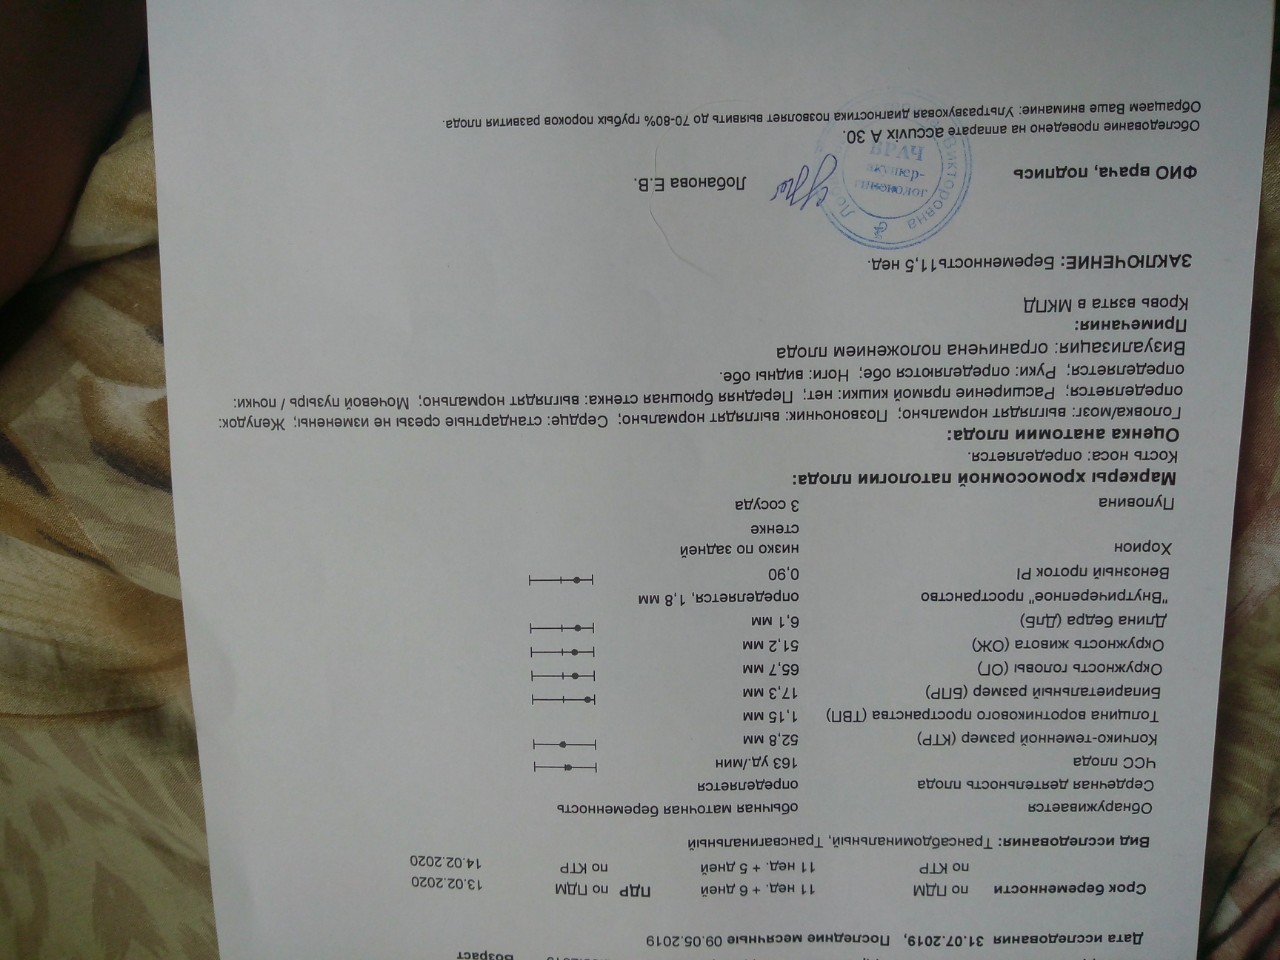

Первый скрининг УЗИ на 13 неделе: Что нужно знать